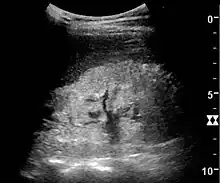

Illustration of a kidney from a person with chronic renal failure

Ultrasound

Kidney ultrasonography is useful for diagnostic and prognostic purposes in chronic kidney disease. Whether the underlying pathologic change is glomerular sclerosis, tubular atrophy, interstitial fibrosis, or inflammation, the result is often increased echogenicity of the cortex. The echogenicity of the kidney should be related to the echogenicity of either the liver or the spleen (Figure 22 and Figure 23). Moreover, decreased kidney size and cortical thinning are also often seen and especially when disease progresses (Figure 24 and Figure 25). However, kidney size correlates to height, and short persons tend to have small kidneys; thus, kidney size as the only parameter is not reliable.[54]